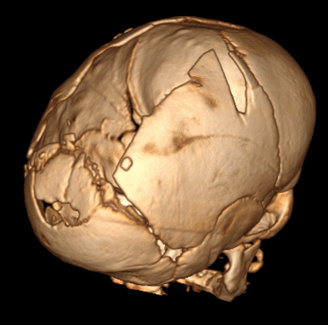

Рис. №2 а) – вариант нормы

б) – деформация черепа вызванная синостозом (слиянием) лямбдовидного шва слева, указателем показаны множественные пальцевые вдавления (истончение костной ткани, вплоть до появление «дыр»).